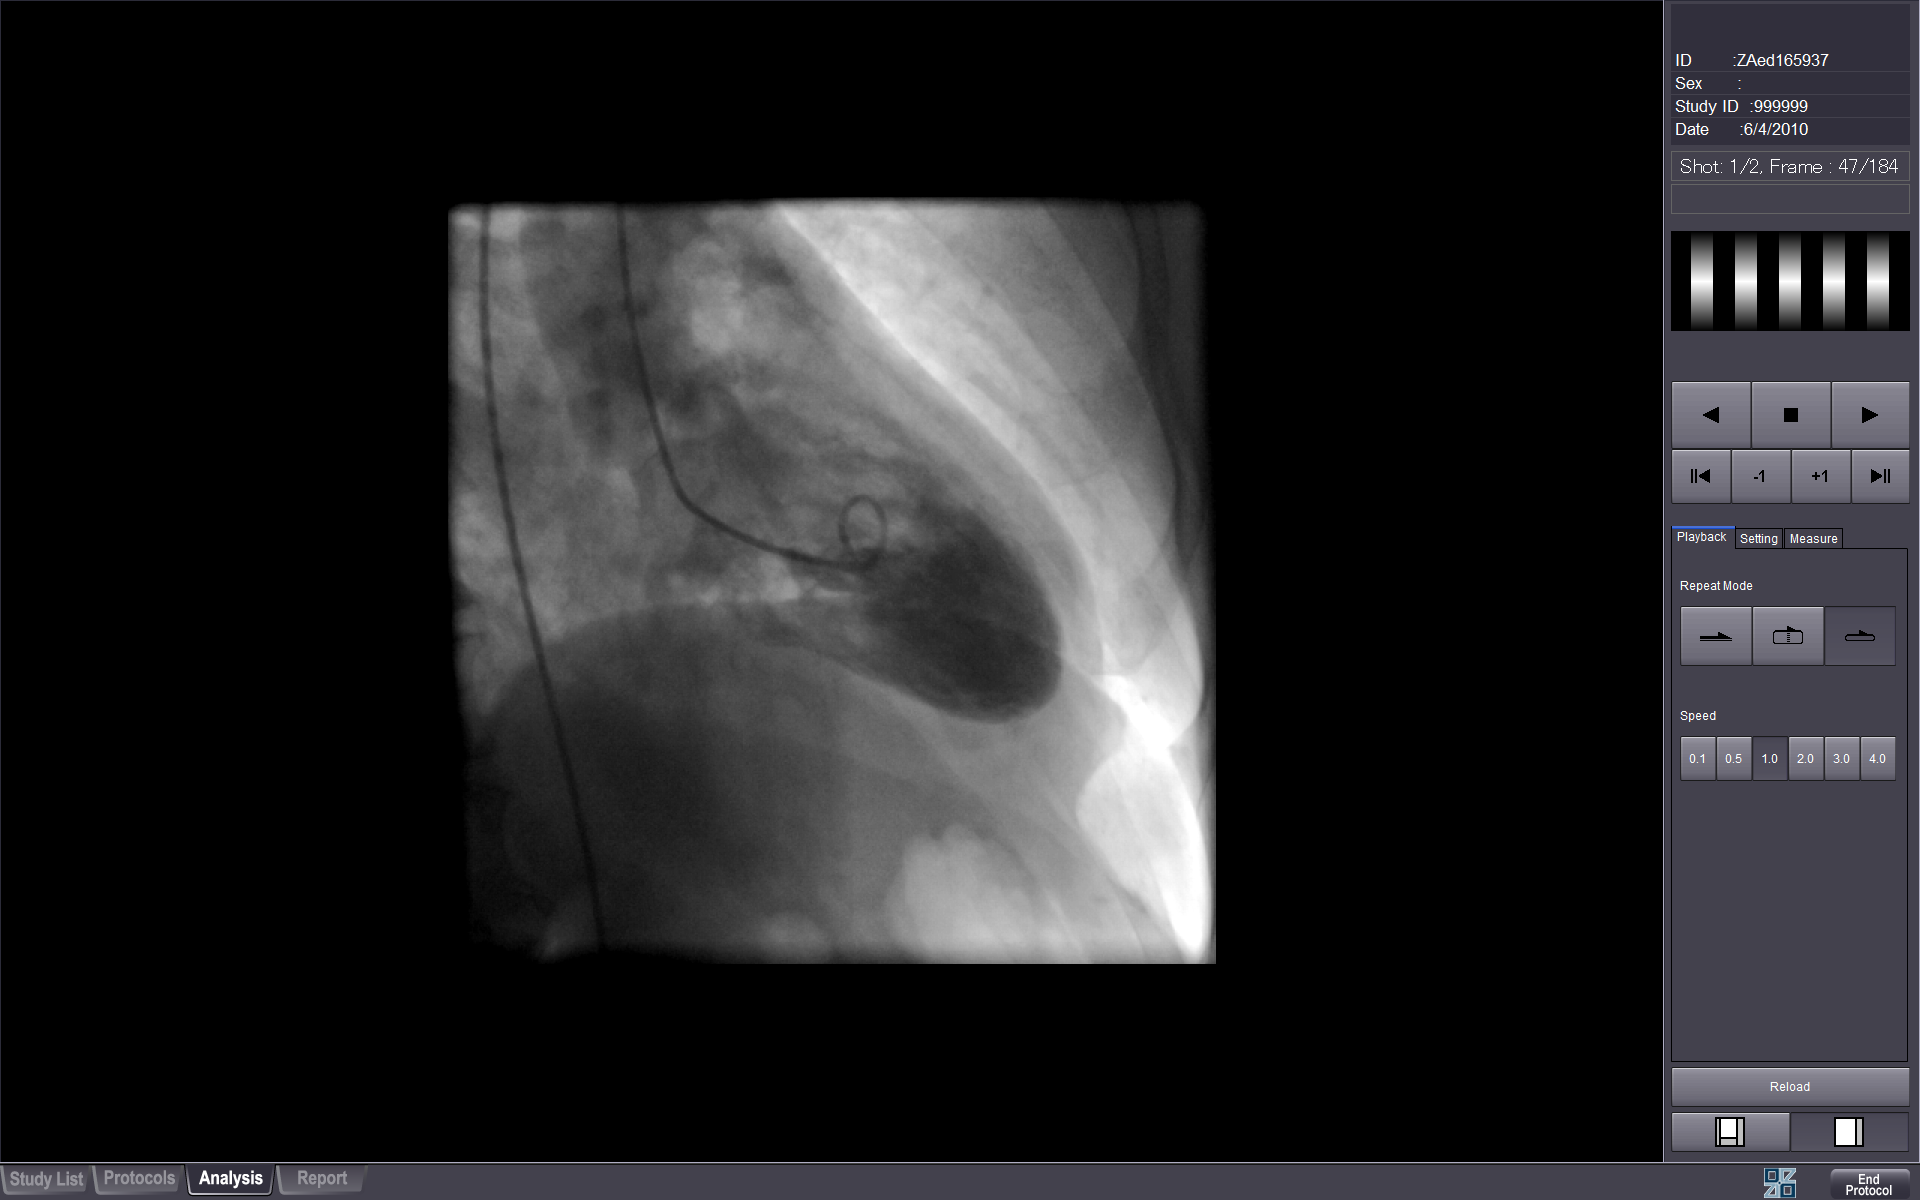

CINE VIEWER

View multi-frame angio data. Features include cine playback, changing playback speed and simple measurements.